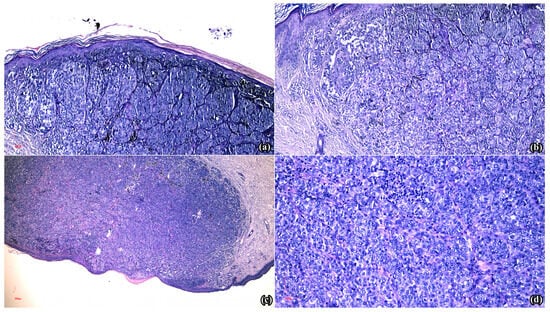

Immuno-histochemical testing was considered appropriate, hence a panel comprising seven antibodies was used (Table 1).

S100 (Figure 2a), PAN MELANOMA CK2 (Figure 2b) and SOX-10 (Figure 2c) displayed diffuse positive reactions. P16 had present expression in the cytoplasm and sporadically in the nuclei (Figure 2d), while CD8 revealed positive reaction in the intra- and peritumoral infiltrate (Figure 2e). Moreover, HMB-45 determined positive reaction in the intra-epidermal, superficial dermal areas and focal absent expression in the deep dermal melanocytic population, suggestive of paradoxical maturation (Figure 2f). Finally, Ki-67 generated positive nuclear reactions of variable intensities, ranging from 5% in the tumor on the left shoulder (Figure 2g) to 25% in the right lateral cervical lesion (Figure 2h).

Figure 2. Microscopical aspects of the immuno-histochemical reactions obtained in the analyzed specimens: (a) Diffuse positive reaction in the melanocytic population (S100 × 5); (b) Diffuse positive reaction in the melanocytic proliferation (MelanA × 10); (c) Diffuse positive nuclear reaction in the neoplastic population (SOX10 × 5); (d) Present expression in the cytoplasm and sporadically at the nuclear level in the melanocytic population (p16 × 20); (e) Positive reaction in the intra- and perilesional lymphocytic infiltrate (CD8 × 10); (f) Positive reaction in the intra-epidermal and superficial dermal component, and focal absent reaction in the deep dermal proliferation (HMB45 × 10); (g) Positive nuclear reaction in 5% of the melanocytic population (lesion from the left shoulder, Ki-67 × 10); (h) Positive nuclear reaction in 25% of the melanocytic population (lesion from the right lateral cervical region, Ki-67 × 10).